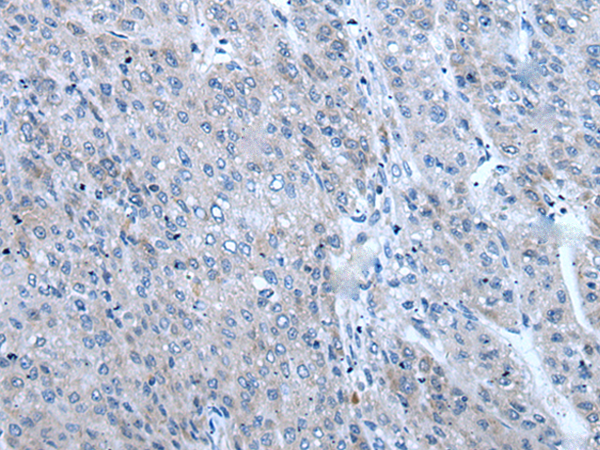

分类: 科研抗体货号: P12842别名: HF10; HF.10; Zfp105应用: IHC反应种属: Human